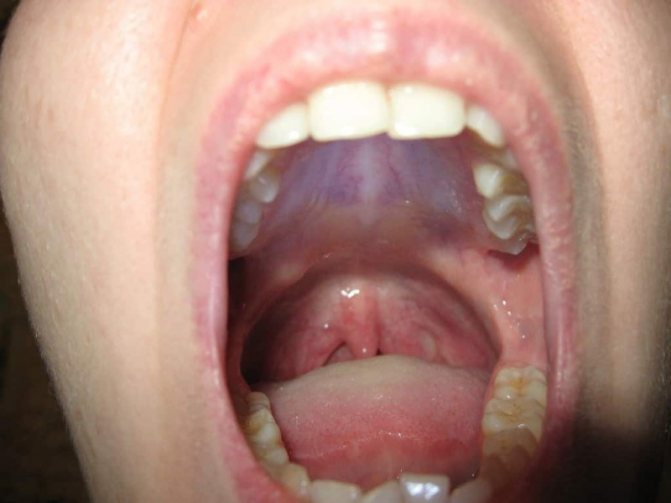

Нарост на десне.

Обычно данный нарост не доставляет человеку болевых ощущений, но он причиняет существенный дискомфорт и нарушает эстетичность, т.к. заметен при разговоре и улыбке. В случае, когда образование запущено или перешло в злокачественное состояние, специфика симптоматики усиливается (все признаки ухудшают общее состояние, они неприятны и довольно болезненны).

Внешний его вид определяется следующими параметрами:

- Формой – ее сопоставляют с грибом, поскольку у образования отчетливо различается ножка (участок, которым он прикрепляется к десне) и тело (похоже на грибную шляпку).

- Размером – всегда зависит от морфологической и клинической формы, и может варьировать от 2-3 мм (его почти не видно) до нескольких сантиметров.

- Цветом – зависит от разновидности нароста. Так, фиброзный идентичен по окрасу с десной, гигантоклеточная – буро-коричневая или синюшная, ангиоматозный – бывает от ярко-красного до темно-красного. Если его часто травмировать пломбой, зубами, протезными кламмерами, его поверхность сильно изъявляется и изменяет окрас.

- Консистенцией – в зависимости от вида клеток, которые послужили источником его роста, плотность бывает разной: мягкой или твердой.